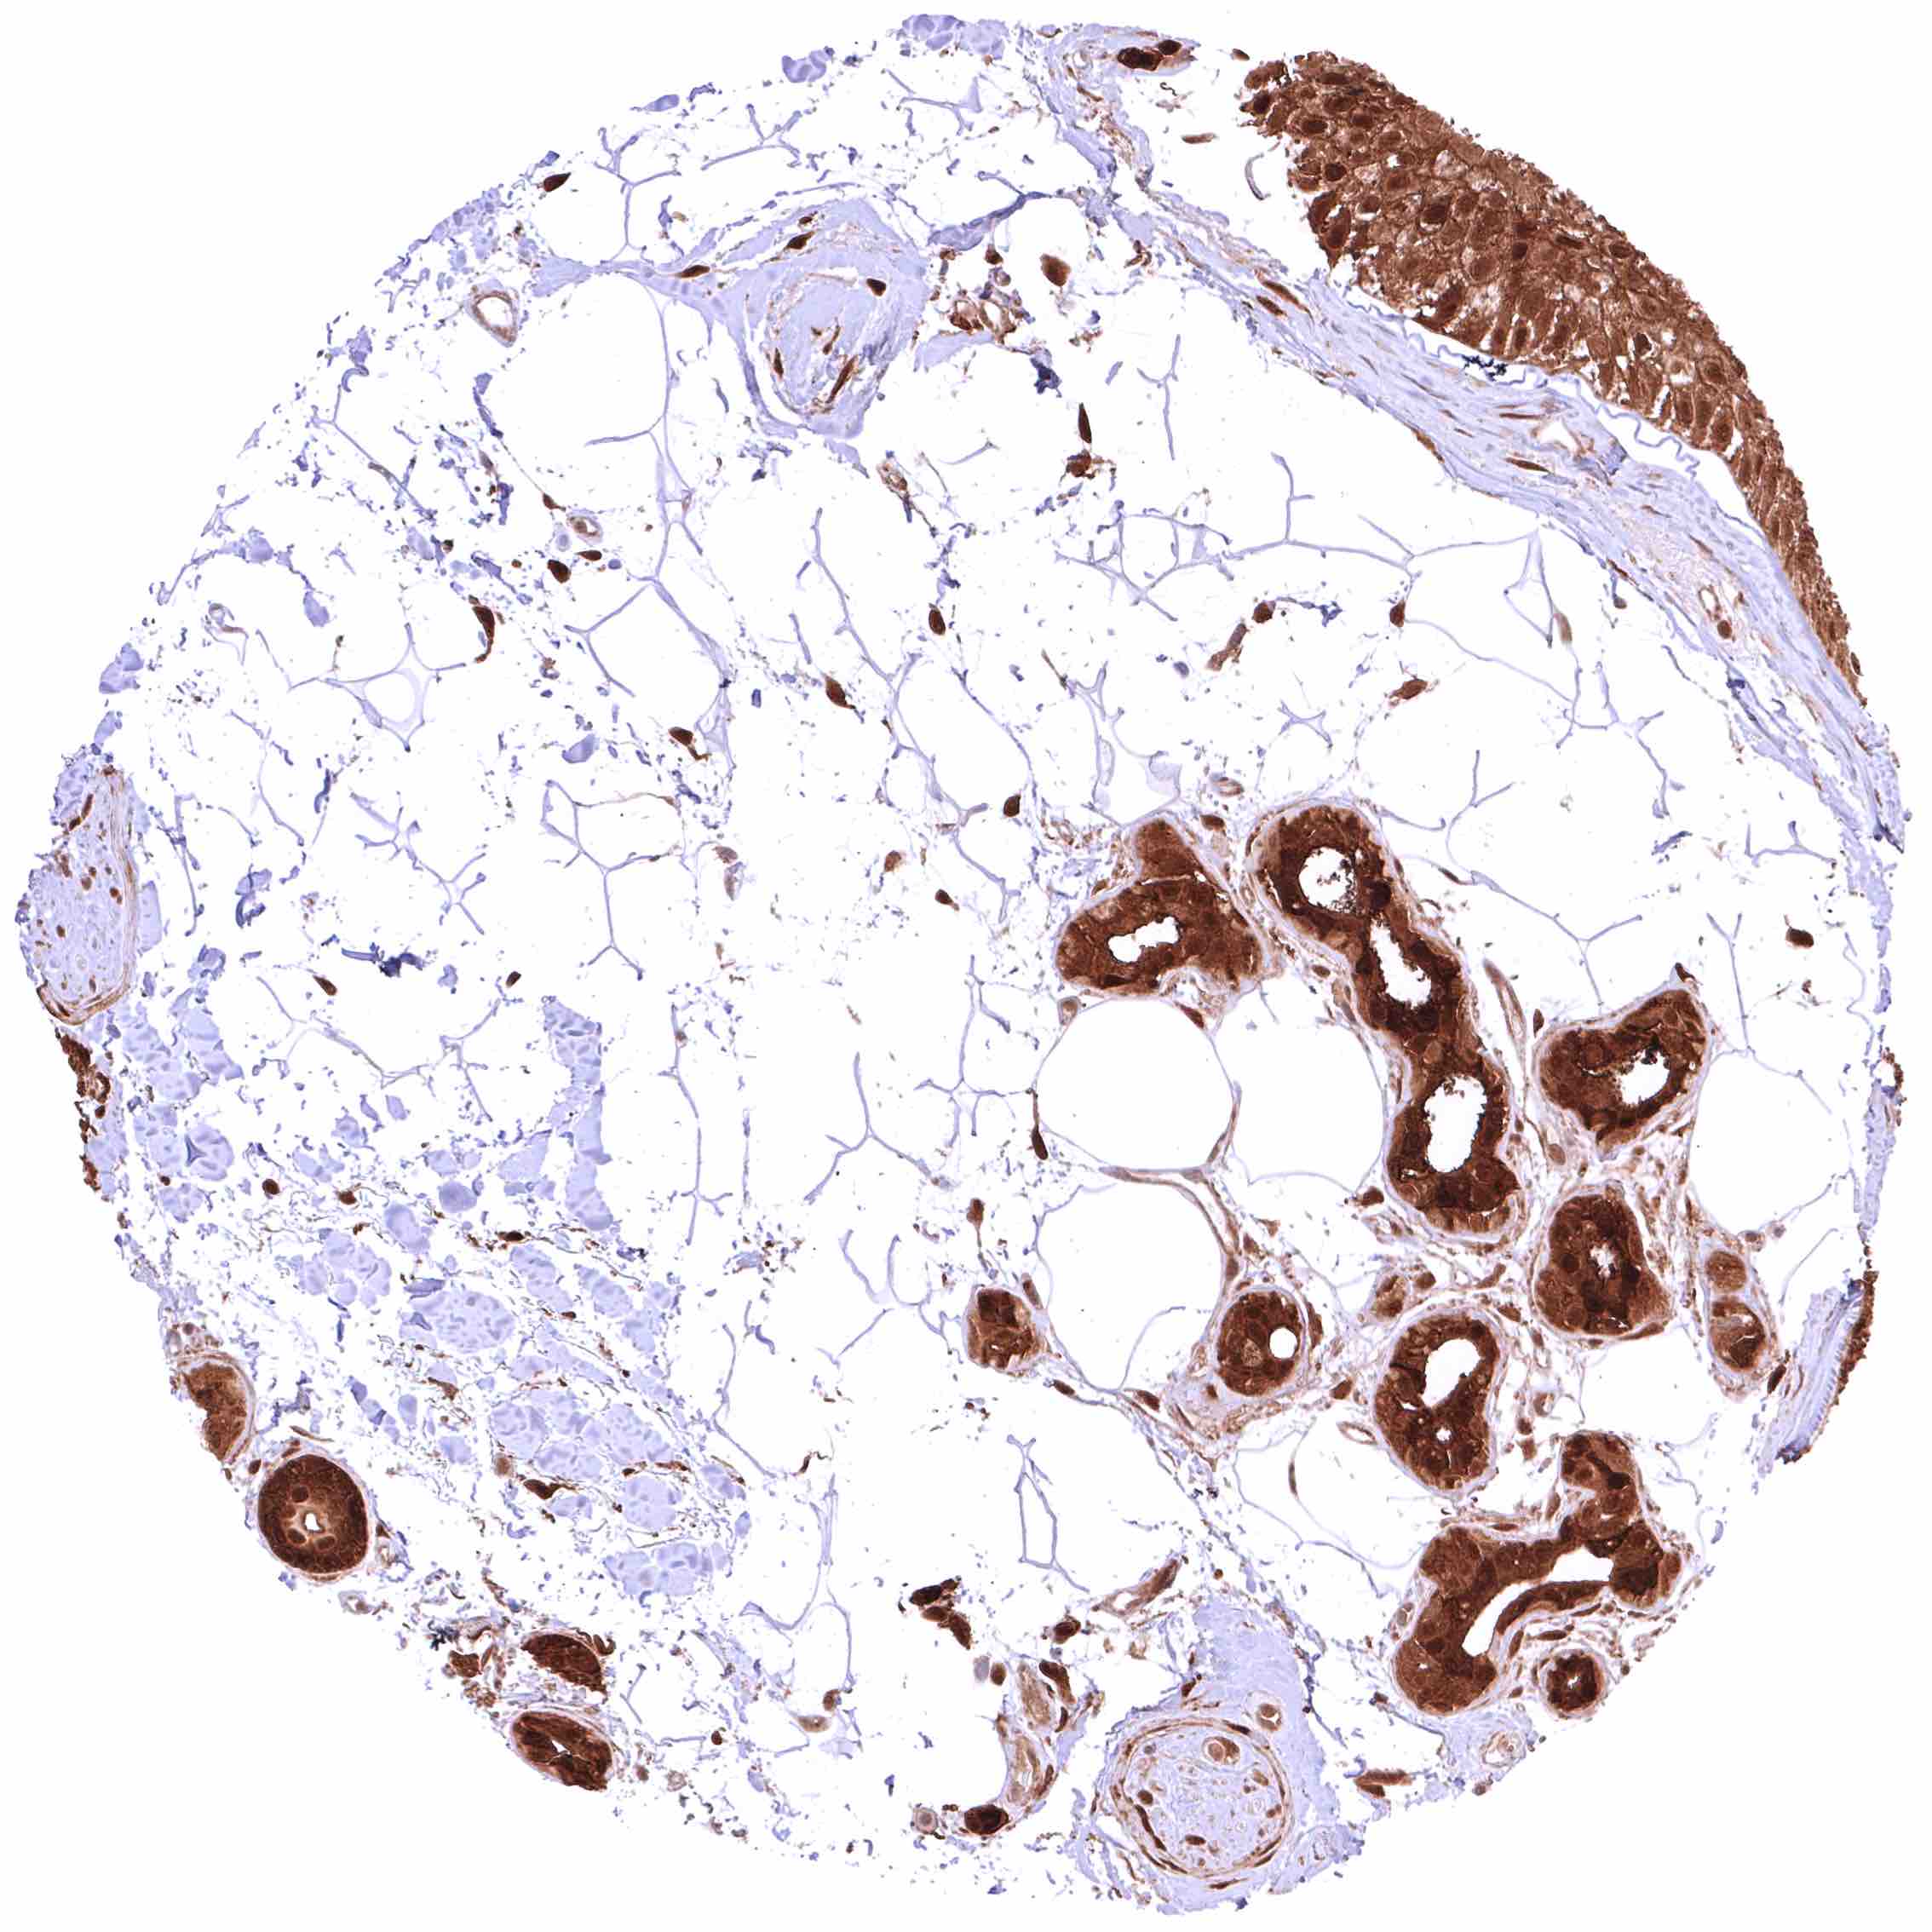

Lung – Moderate, predominantly cytoplasmic positivity of alveolar endothelial cells. Strong, nuclear and cytoplasmic GSTP1 positivity of at least a significant subset of alveolar cells.